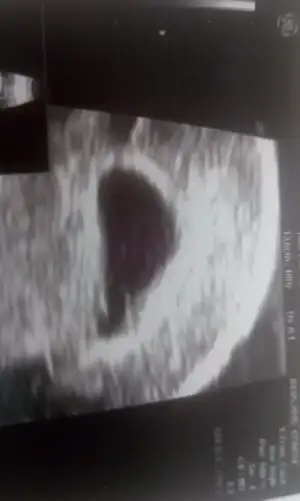

- Konu Sahibi Nurbebekistiyor

- #1.861

Yaaa sorma bende sürekli hapsırıyorum kasıklarım çok fena oluyor 5 saniye kadar kıvranıyorumtamam bebegim vetoyu koyarim ben yazik adamla yeni evliyiz onda aciyom neyse bebis icin dayansin istemeyi bilio ama :--)))buarada hapsirinca kasiklarim ck agrio sizdede oluyo mu bide bahar surekli hapsiririm ben